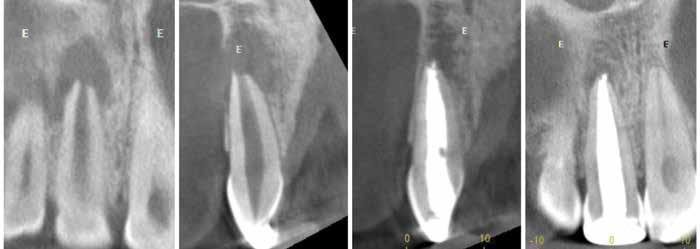

Proton density (left) and CBCT (right) images of apical lesion and furcation involvement at tooth #2. This tooth was clinically diagnosed with pulpal necrosis and a crack involving the furcation.

Proton density image showing improved image detail provided by dental dedicated MRI coil.